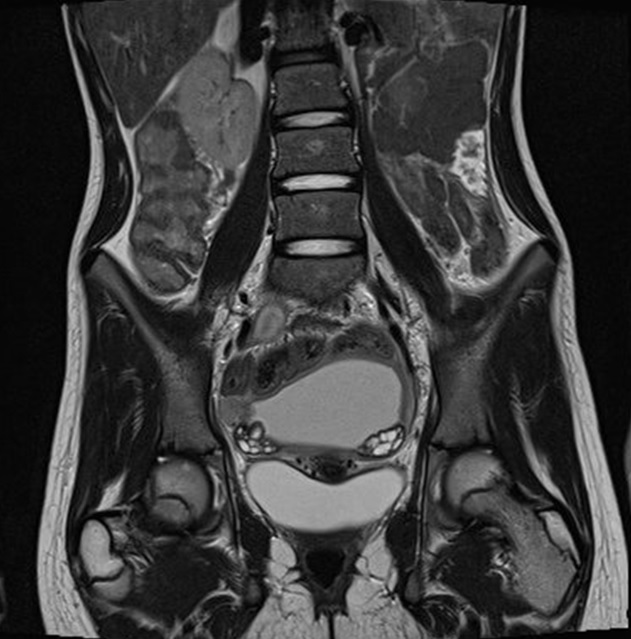

МРТ малого таза (магнитно-резонансная томография) – совершенно безопасный метод исследования, позволяющий выявить причины нарушения репродуктивной и мочеполовой системы мужчин и женщин.

Во время исследования состояние брюшной полости можно увидеть на высокоточной диагностической картинке. МРТ позволяет сделать недорого диагностику практически любой системы в организме, при этом очень быстро и достоверно. Врач легко определяет состояние лонной кости и поясничных костей позвоночника, что показывает наличие или отсутствие метастазов, либо имеющуюся опухоль, например, прямой кишки.

Исследование женских органов

МРТ женских органов позволяет узнать о состоянии:

- матки с придатками (сюда входят маточные трубы, яичники);

- влагалища;

- мочевого пузыря;

- прямой кишки (и окружающих ее мягких тканей, лимфатических узлов и сосудов).

По результатам этого исследования андролог (а у женщин гинеколог) сможет увидеть участок распространения патологических процессов, возможные изменения в лимфатических узлах или окружающих тканях.

Важно то, что противопоказаний практически нет, и проводить МРТ можно много раз без вреда для здоровья пациента. Достоверность результатов обеспечивается тем, что исследуемый орган показывается послойно, и это позволяет отметить даже только зарождающиеся отклонения от нормального состояния.